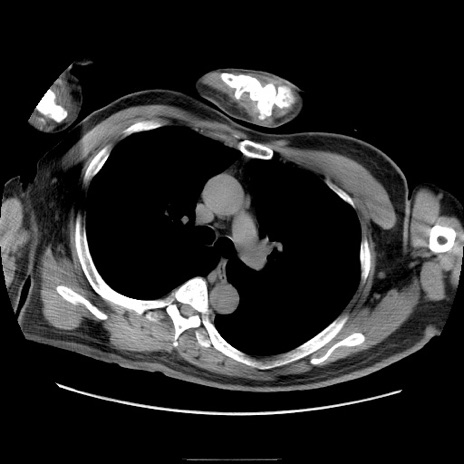

冠状断像

【症例】50歳代男性

【主訴】腹痛

【現病歴】AVMからの被殻出血のため回復期リハ病棟入院中。 本日午後3時頃急に下腹部痛が出現した。

【既往歴】AVM、被殻出血、虫垂炎、高血圧

【身体所見】意識晴明、左半身不全麻痺、会話の理解は良好、36.5°C、腹部:膨隆、全体に板状硬、下腹部正中に圧痛点あり、反跳痛-、筋性防御不明、右下腹部にope scar

【データ】WBC 9400、CRP 0.06